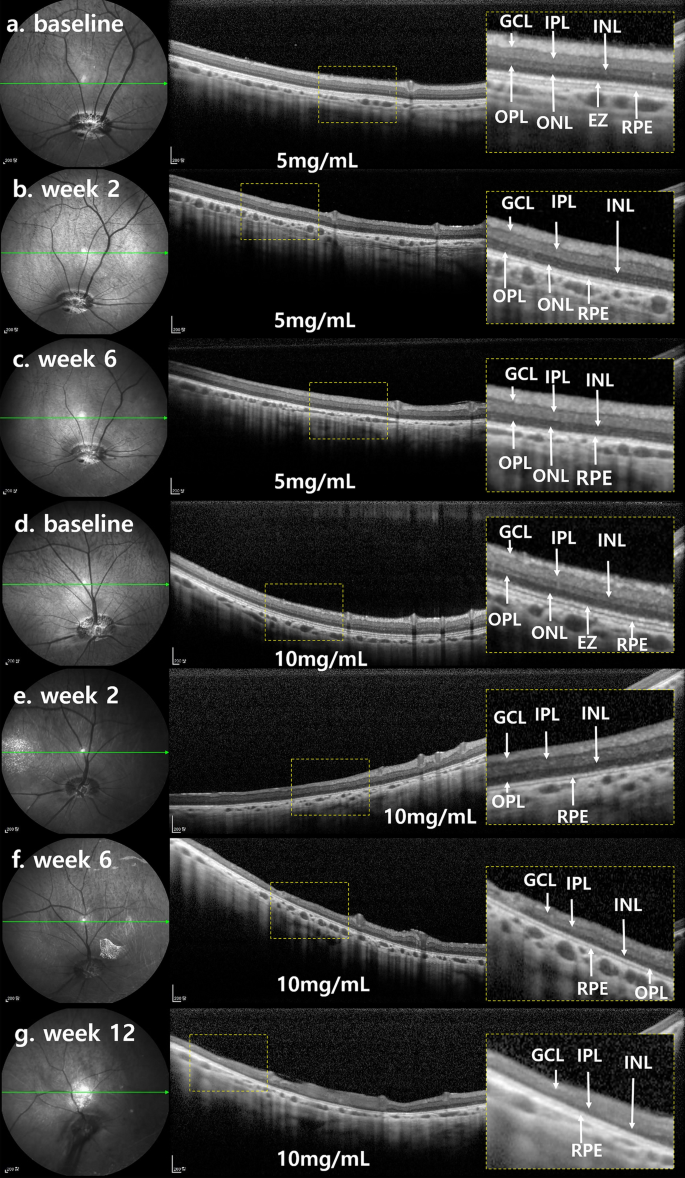

SD-OCT images at week 2 showed intact GCL and RPE. The ellipsoid zone on 55-degree SD-OCT fields was barely distinguishable at week 2 (Fig. 6), and outer plexiform layer thickness decreased. From week 2 to week 6, subsequent changes were minimal and similar among layers. Mean thicknesses of INL, ONL, and TRL showed significant decrease at week 2. From week 2 to week 6, changes were minimal (Fig. 7, Table 2).

SD-OCT finding of each representative case of 5 mg/mL MNU and 10 mg/mL MNU. (a–g) Each magnified SD-OCT image of the case is from the right side and shown with a dashed-line box. (a–c). OCT images of a representative case with moderate outer degeneration in the 5 mg/mL group. (a,b) OCT images at week 2 showed intact GCL and RPE. The EZ was indistinguishable at week 2. In addition, there was a decrease in OPL thickness. (c) OCT images remained stable at week 6 compared with the results of week 2. (d–g) OCT images of a representative case with severe outer degeneration in 10 mg/mL group. (d,e) On the OCT, unlike baseline, the ellipsoid zone was indistinguishable at week 2. In addition, there was a decrease in INL thickness and ONL. (f,g) OCT image at weeks 6 and 12 showed no significant change compared with the results of week 2. However, the signal intensity of OCT decreased at week 12 due to anterior capsular opacity. SD-OCT spectral domain optical coherence tomography, GCL ganglion cell layer, IPL inner plexiform layer, INL inner nuclear layer, OPL outer plexiform layer, ONL outer nuclear layer, EZ ellipsoid zone, RPE retinal pigment epithelium.

On SD-OCT, the EZ was indistinguishable at week 2. The thicknesses of INL, ONL, and TRL appeared to decrease at week 2 (Fig. 6). Further losses of INL and ONL were not detected at week 6 or 12. In addition, there was decrease in mean thicknesses of INL, ONL, and TRL. From week 2 to week 12, each mean thickness showed no subsequent changes (Fig. 7, Table 2).